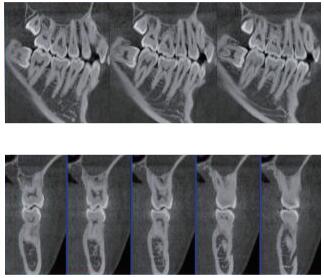

三維重建任意斷層

專有三維重建算法,可提供任意位置高清斷層影像。

專有圖像校正技術(shù),去除金屬偽影,提高圖像分辨率。

多平面組合重建

可同時(shí)觀察軸向面、冠狀面和矢狀面圖像,方便臨床診斷。